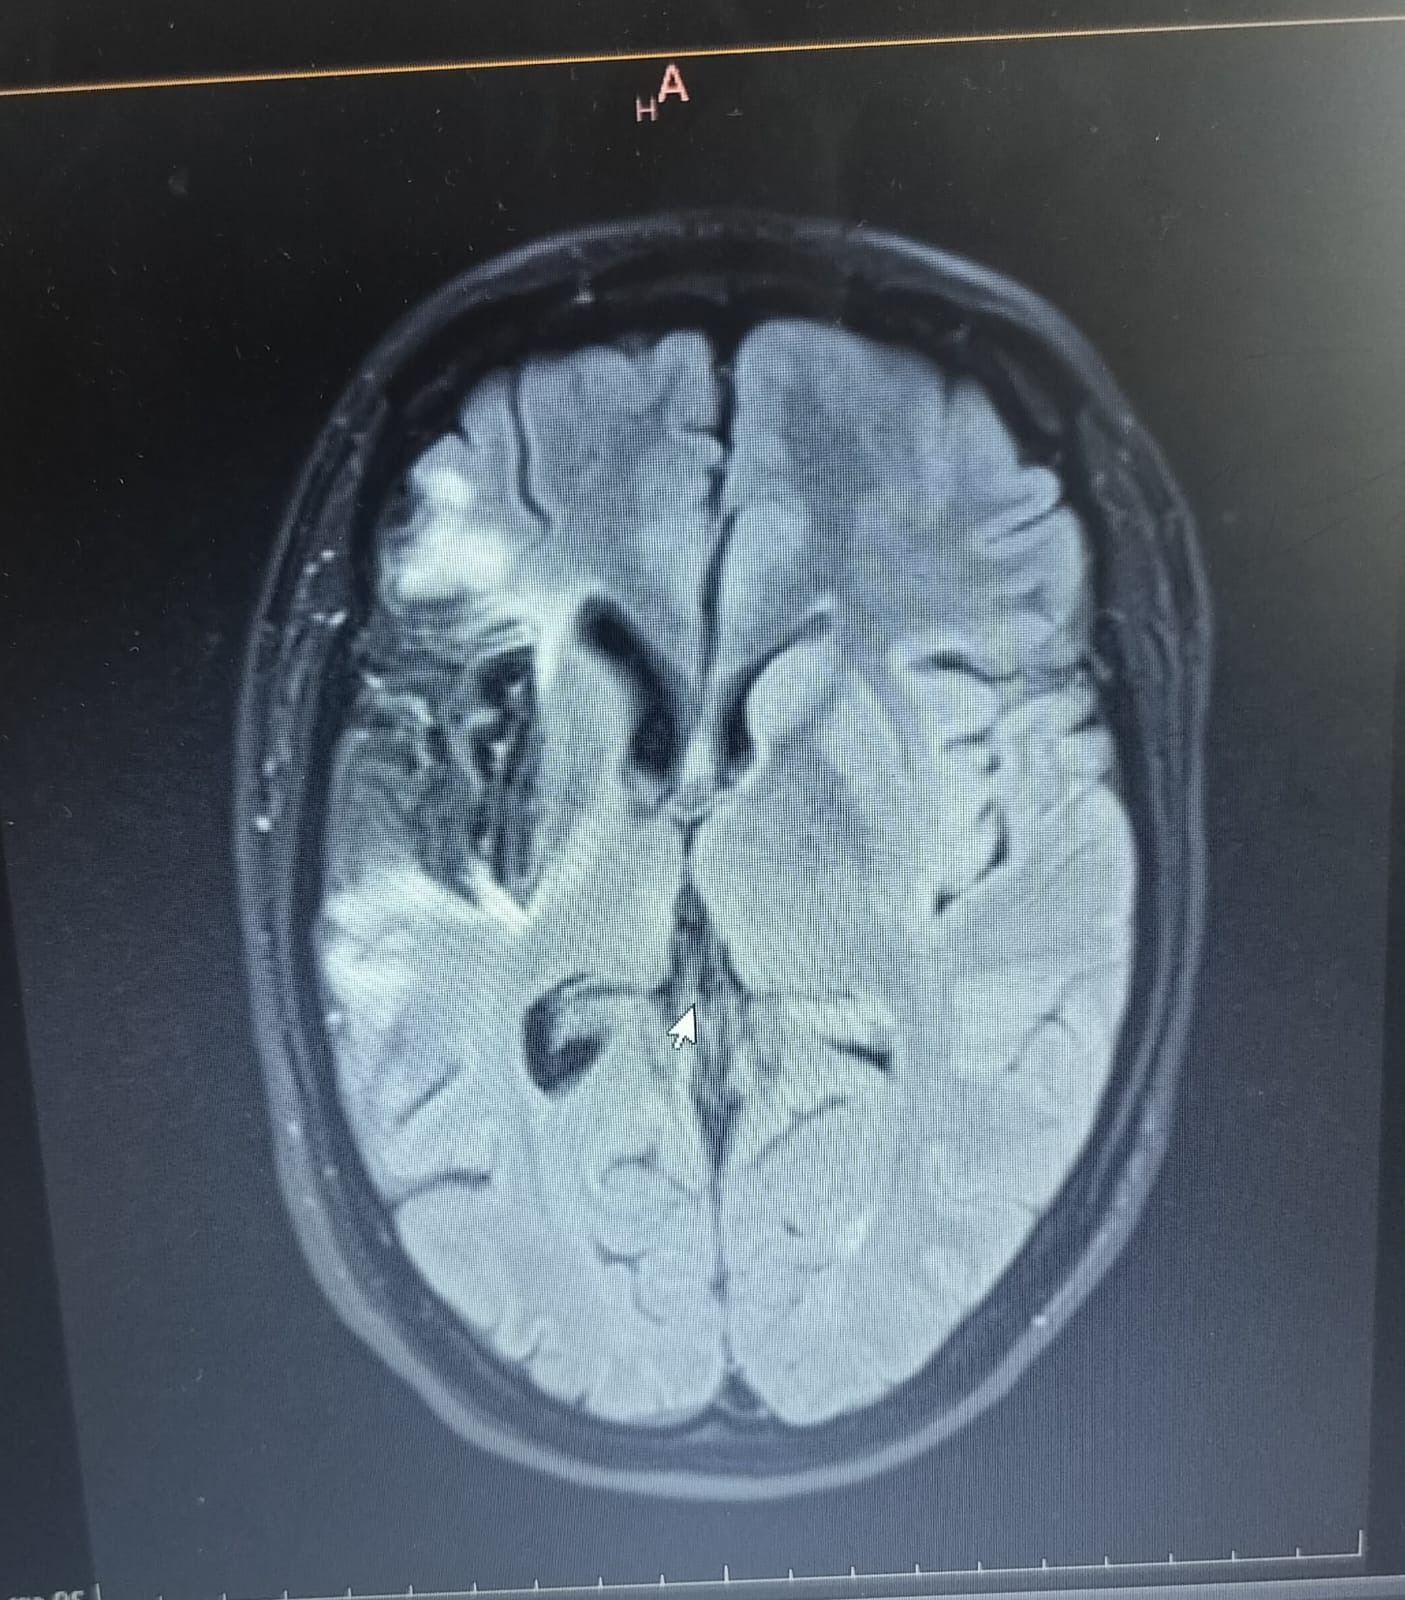

My name is Ian Dahms, I am fundraising on behalf of my wife Kat. Unfortunately she suffered a major stroke at 37yrs old back in September 2024. She now has a condition known as Aphasia which makes it very difficult for her to communicate like she used to. After several difficult months with treatments and speech therapy her mobility has nearly returned but her speech is still suffering.